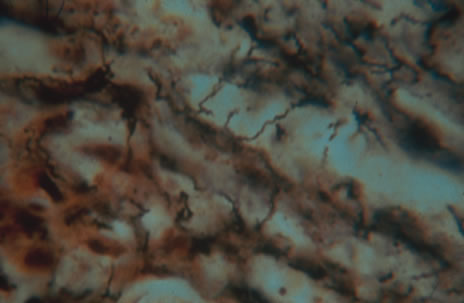

Diagnosis of syphilis is difficult at times and often requires a high level of suspicion because of the varied manifestations of the disease. Syphilis can be diagnosed by examination of material from infectious sores by dark field microscopy (Fig. 21). The organism may be demonstrated with silver stains or direct fluorescent antibody microscopy. Pathology specimens show mononuclear infiltration particularly around blood vessels. The easier and more commonly used route of testing is serologic. Serologic tests can be categorized as either treponemal or non-treponemal. Venereal Disease Research Laboratory (VDRL) and rapid plasma regain (RPR) are nontreponemal tests that detect antibodies to cardiolipin cholesterol antigen. These tests are best suited for general screening, but a positive result must be confirmed with a treponemal test such as fluorescent treponemal antibody absorption test (FTA-ABS).76

Fig. 21. Histopathologic examination of silver stained conjunctival lesion revealed spirochetes.